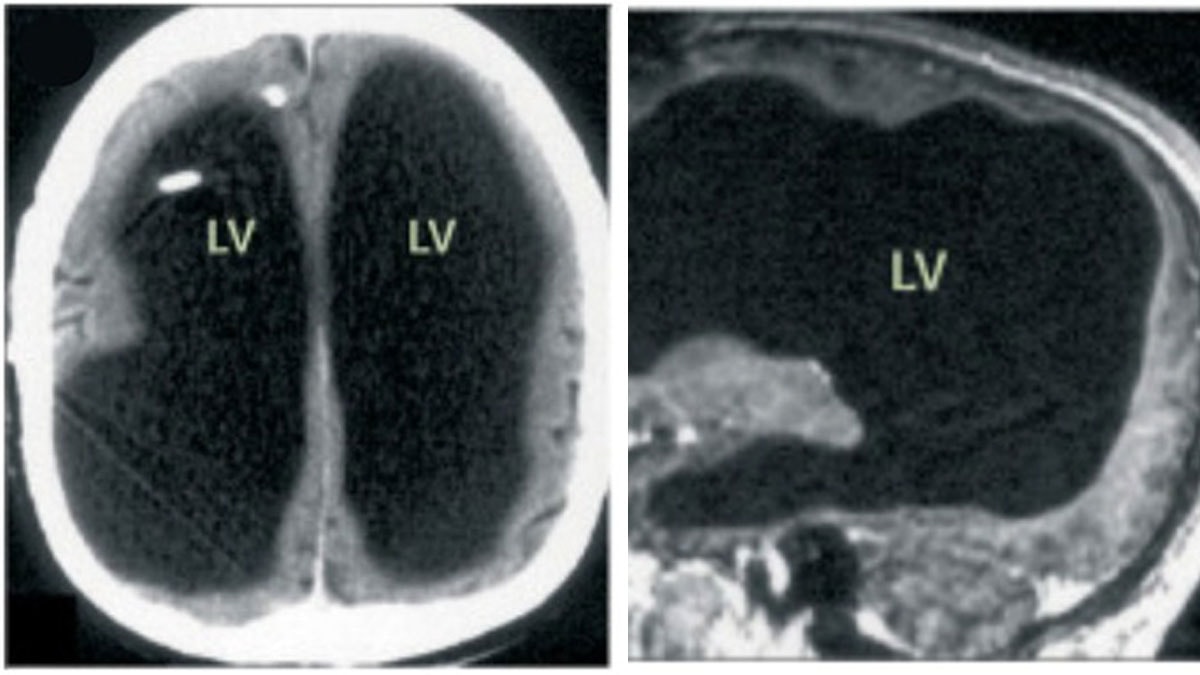

Deneyin öncesinde ve sonrasında manyetik rezonans görüntüleme (MRI) taramaları ve psikolojik testler yapıldı. Telefon kullanımının kısıtlanmasının beyin aktivitesi üzerindeki etkilerini inceleyen araştırmacılar, bağımlılıkla ilişkili nörotransmitter sistemleriyle bağlantılı değişimler tespit etti.

Deney sonunda yapılan MRI taramalarında, katılımcılara açık ve kapalı telefon görüntüleri ile nötr nesneler (örneğin çiçekler ve tekneler) gösterildi. Telefon görüntüleri gösterildiğinde, ödül işleme ve bağımlılık dürtüsüyle bağlantılı beyin bölgelerinde değişimler gözlendi.